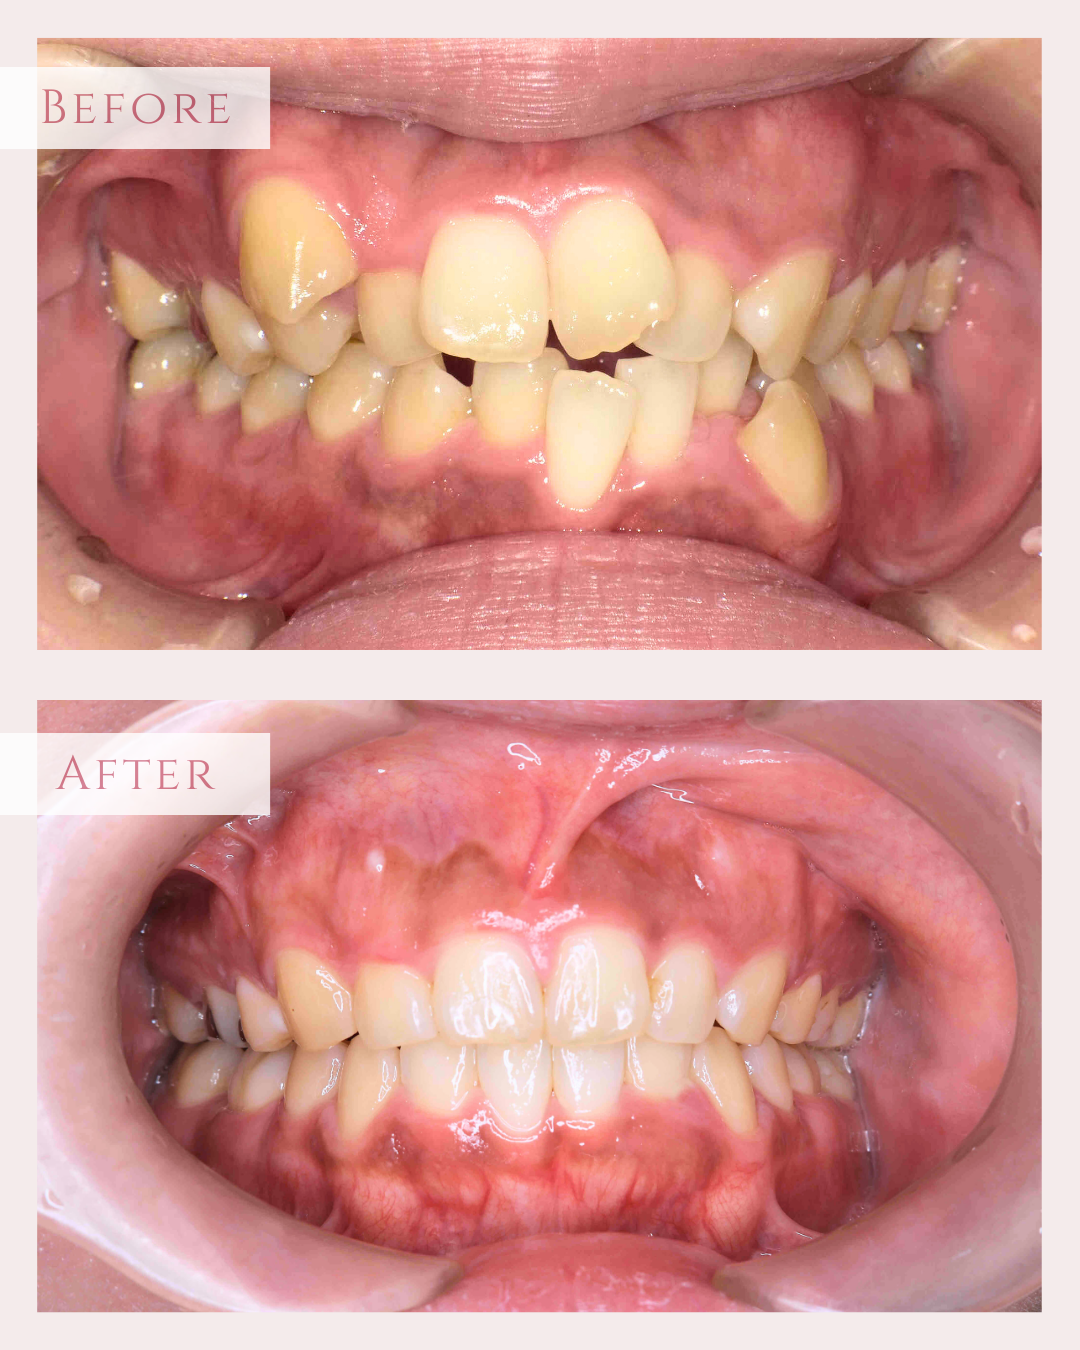

• 治療前

治療後

元々咬む筋力や食いしばり・歯ぎしりが非常に強く、『フレアーアウト』(前歯の歯並びが前方に放射状に倒れていく現象)によって「出っ歯」や「すきっ歯」の状態になっていました。

歯並びの問題だけでなく、顔つきが変わったり、前歯で食べ物を噛むことが難しくなるなど、機能面にも支障をきたします。

今回はご希望のマウスピース矯正で、食いしばりや歯ぎしりによる歯の破折やすり減りを予防しながら、歯と歯の隙間が広がって傾斜した前歯を元の位置に戻しました。

ホワイトニングも同時進行で施術し、白く輝く歯になりました。

元々入っていた臼歯のブリッジは治療せず、そのままの位置で矯正を行うことを希望されたため、正中(上顎と下顎の中心線)を合わせることは難しいですが、美しい歯列と口元へ仕上がりました!